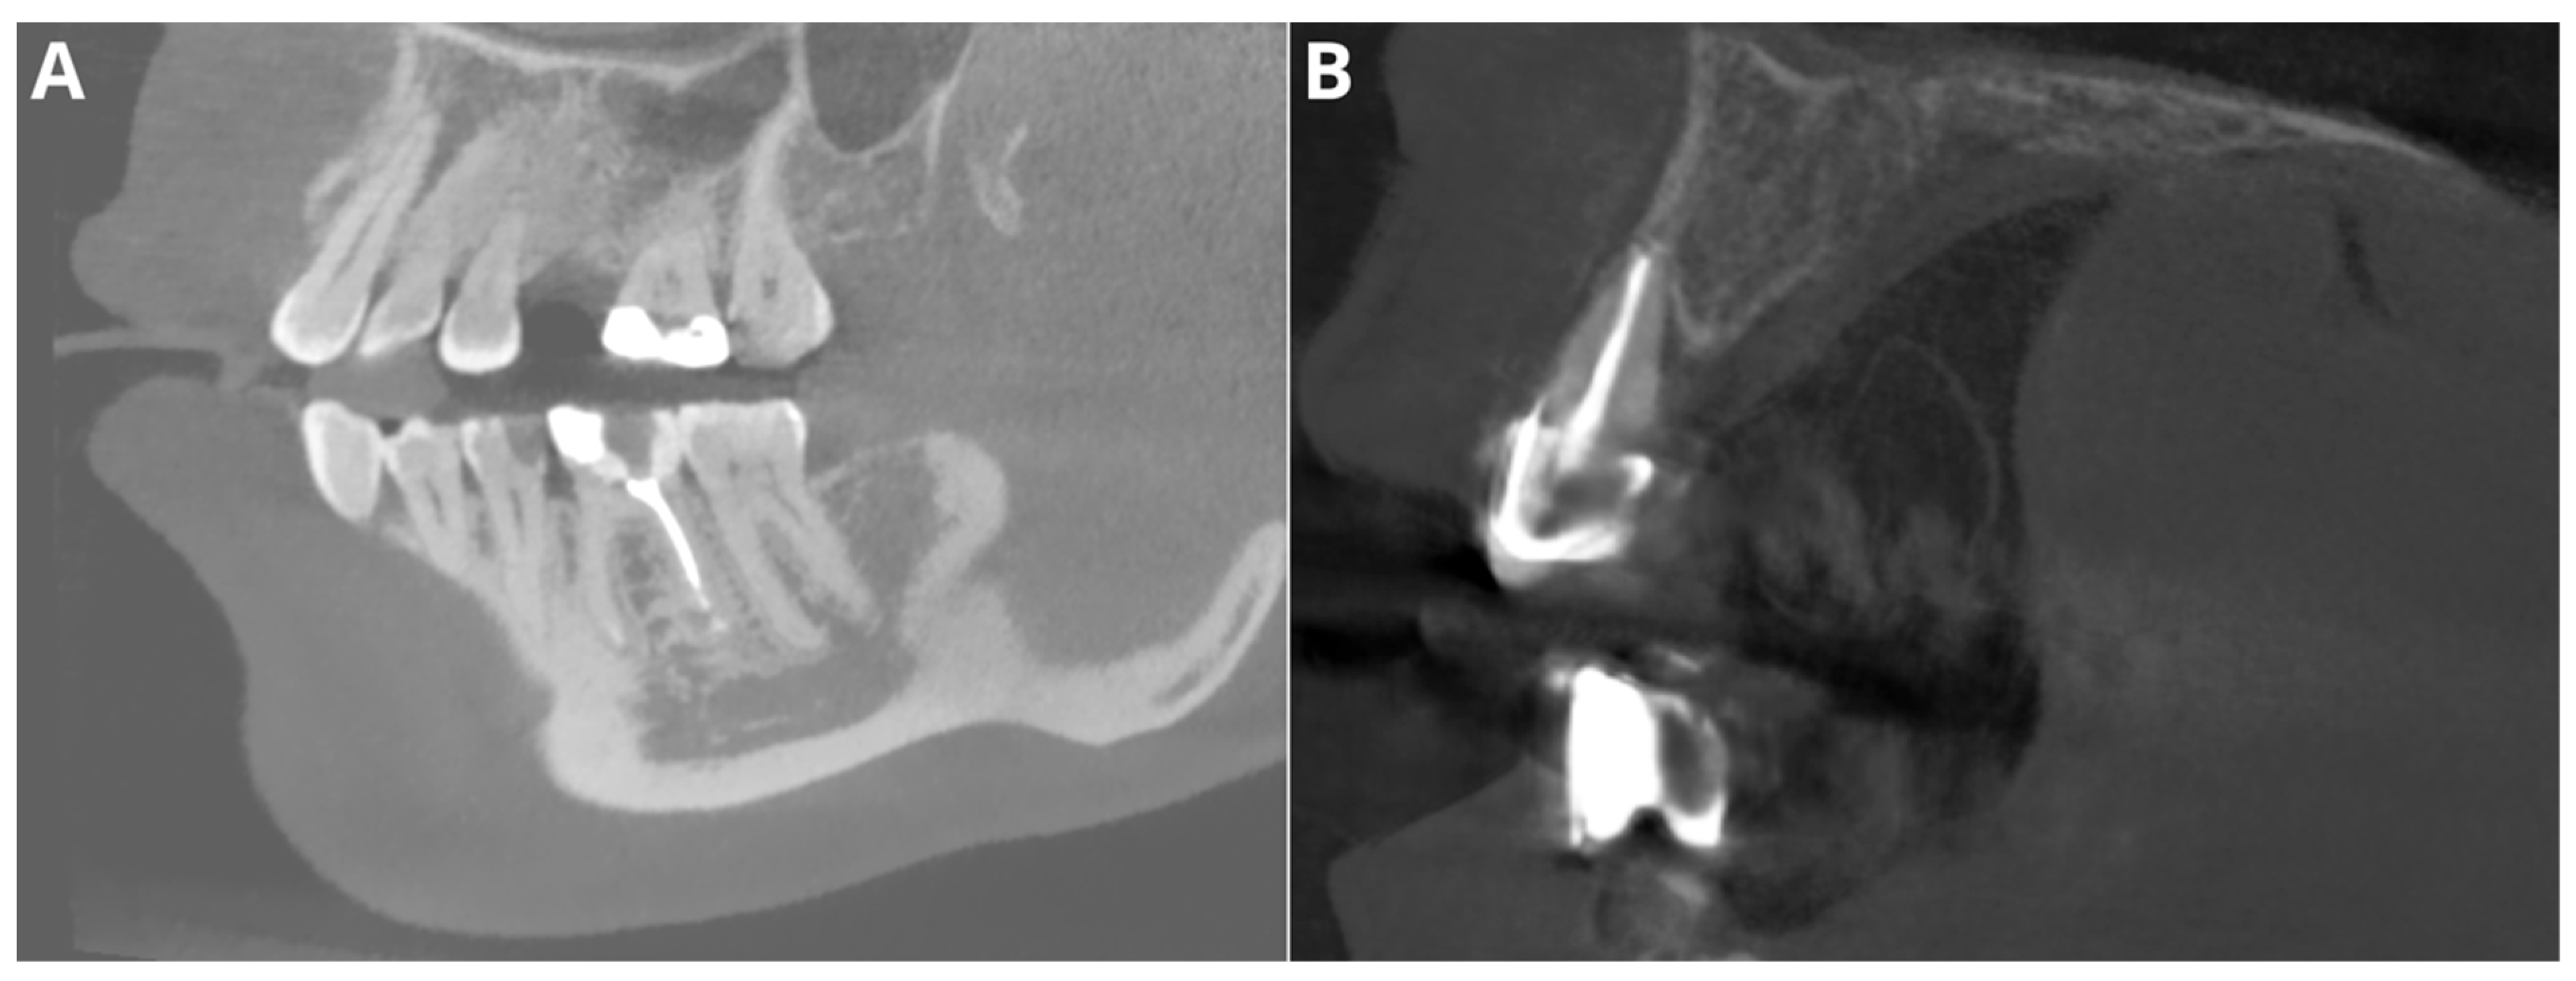

The performance for adequate density was notably high, with an accuracy of 95.5%, a precision of 97.2%, a recall of 97.2%, and an F1 score of 97.2%. Considering that this parameter relies on the subjective evaluation of the readers, we assume that the tested AI program exhibited perfect agreement with the readers’ assessments. Diagnosis revealed overfilling with high accuracy (95.5%), precision (86.7%), recall (100%), and F1 score (92.9%) on the CBCT images. An evaluation of the misdiagnoses revealed that all cases were very subtle (Figure 3). In contrast, Orhan et al. [26] reported a sensitivity of 66.7% for Diagnocat’s overfilling detection on panoramic images. These differences may stem both from the program’s algorithms’ improvements over time and from the different imaging modalities. Moreover, Diagnocat showed exceptional diagnostic accuracy in short-term assessments, with close to 100% accuracy. Figure 4 presents two of the false-negative diagnoses. The detection of voids by the AI program achieved lower performance than other parameters in our study, with 88.6% accuracy, 88.9% precision, 66.7% recall, and 76.2% F1 score. However, Orhan et al. reported a much lower sensitivity of 23.3% for void detection on panoramic images [26]. This discrepancy could be attributed to the 3D imaging provided by CBCT compared to the 2D panoramic images used in Orhan’s study. Our study revealed high accuracy and precision for diagnosing short fillings (95.5% and 100%, respectively), along with a recall of 86.7% and an F1 score of 92.9%. However, Orhan et al. reported a lower sensitivity of 70% [26].

Figure 3. Two of the false negative diagnoses involved overfilling. (A)—tooth 46; (B)—tooth 12.